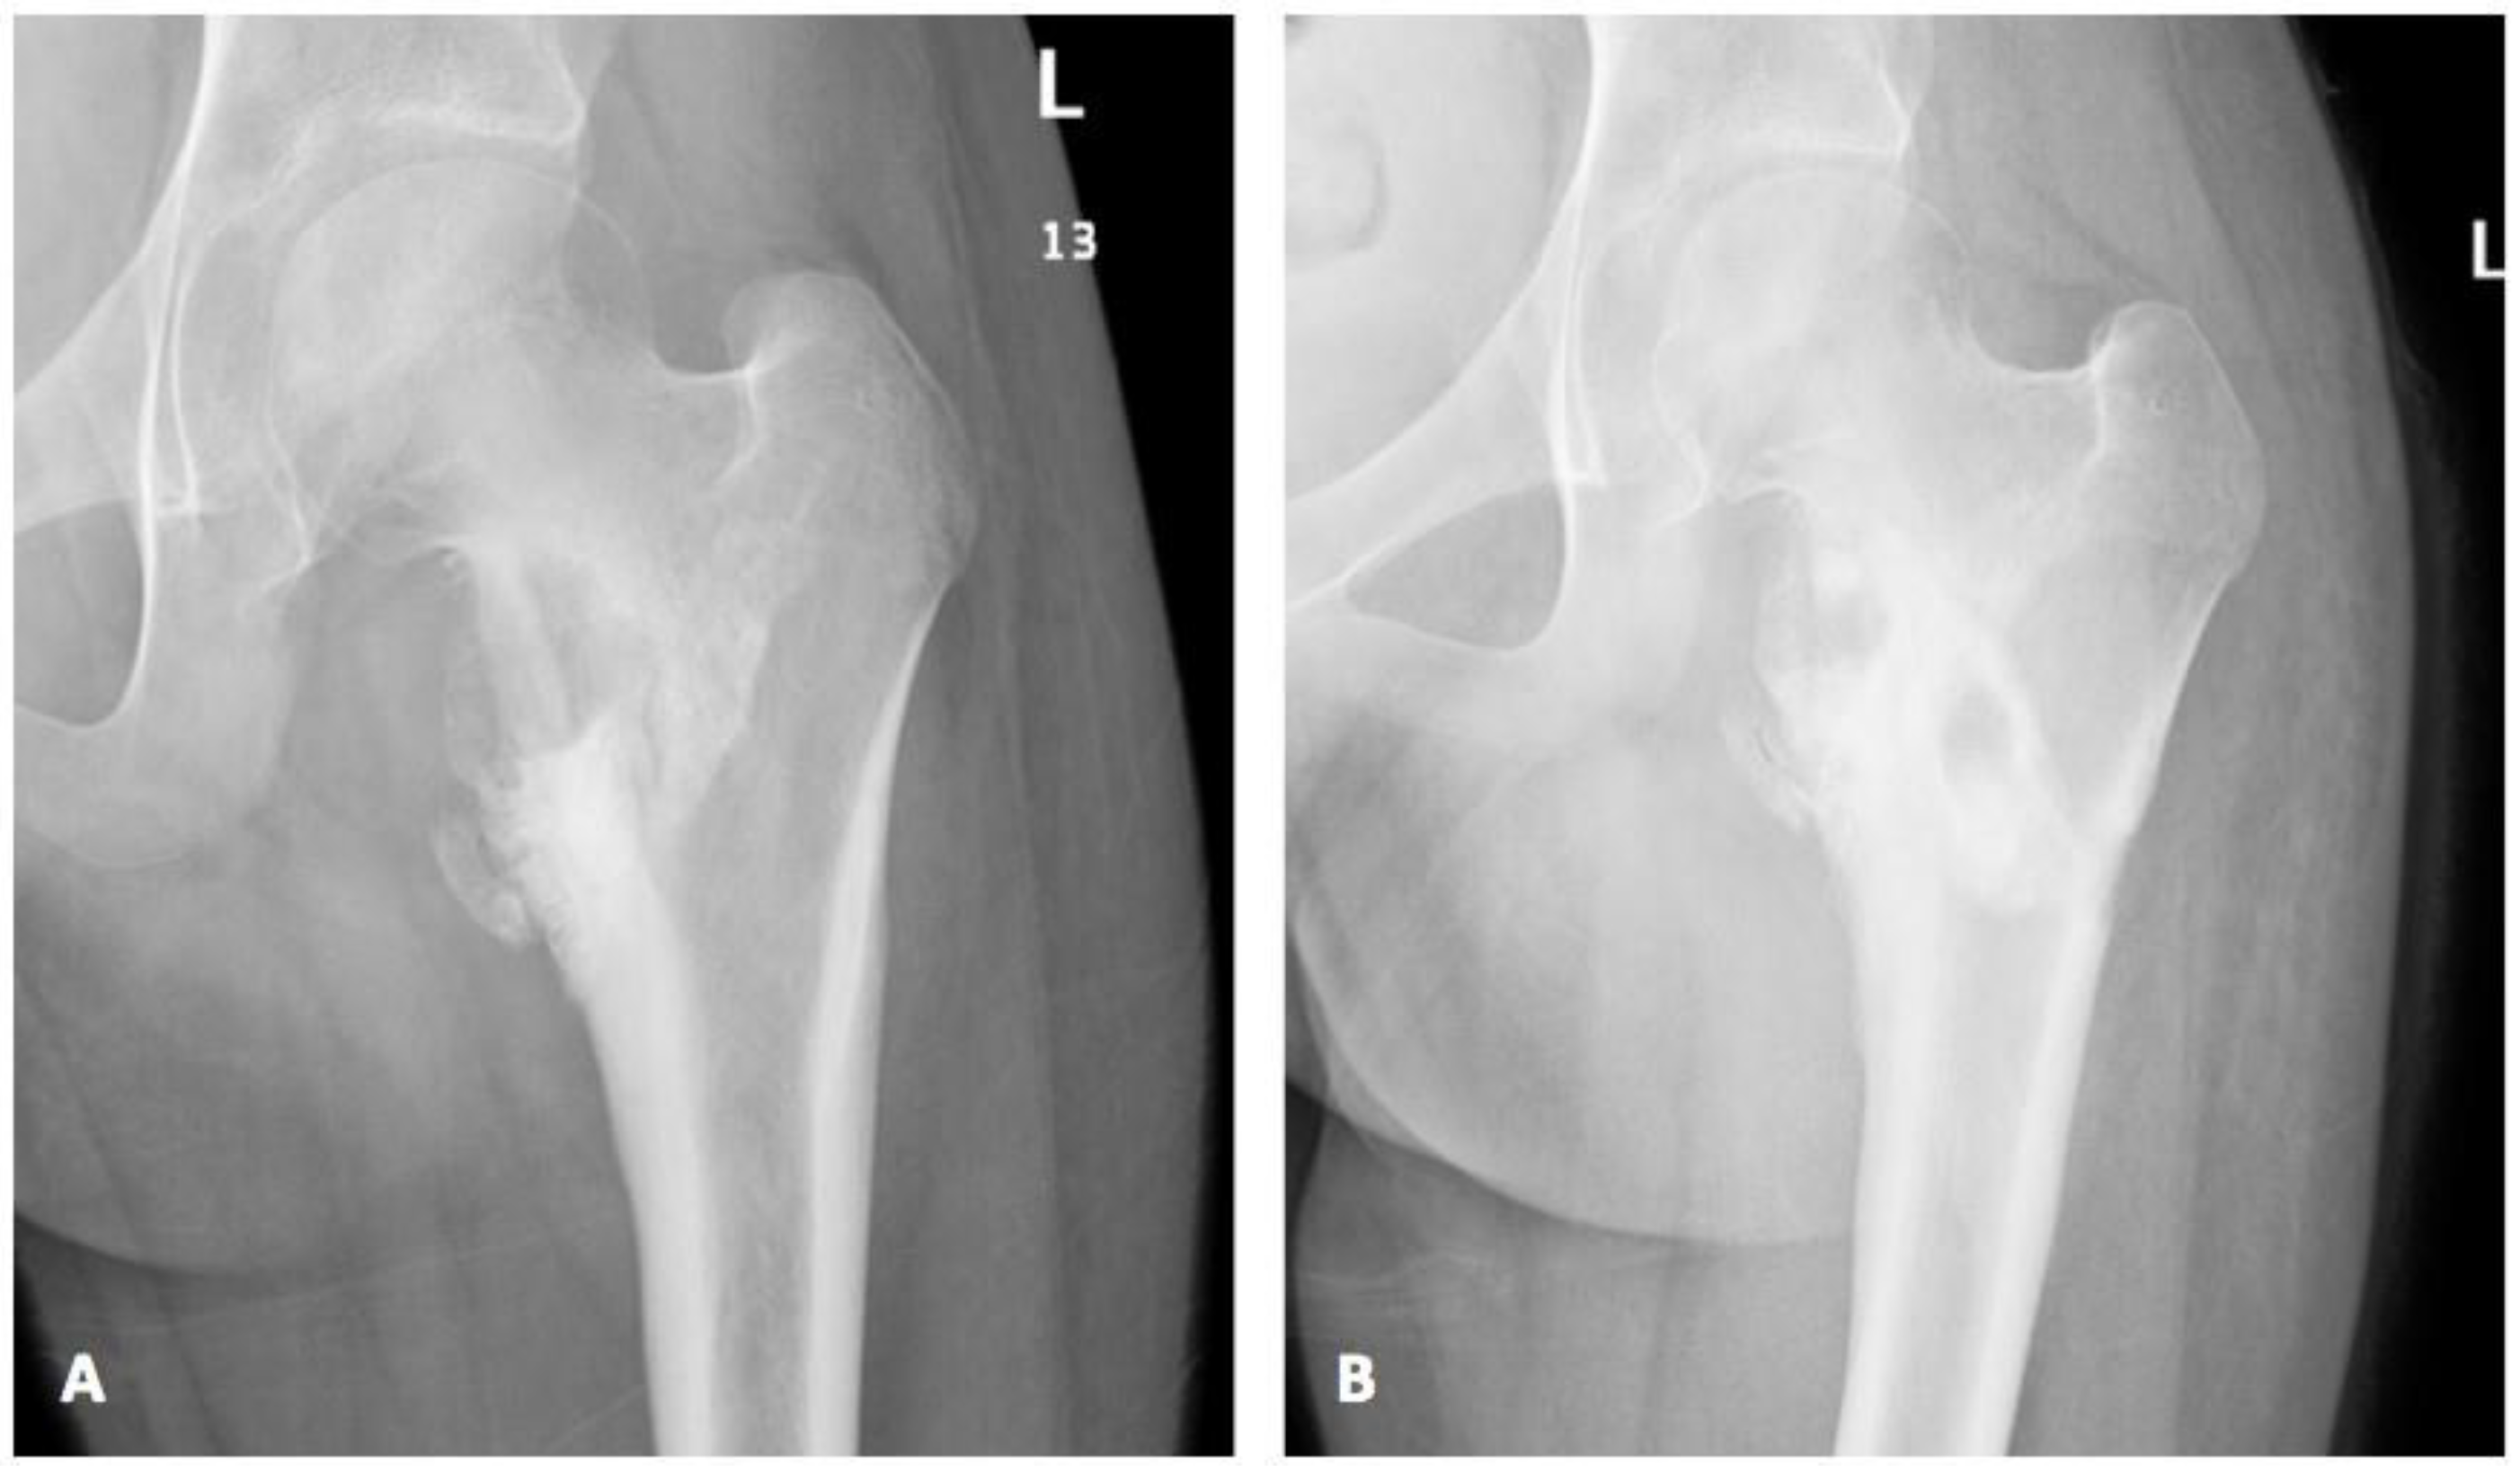

Despite three months of therapy on voriconazole (9 mg/kg/dose twice daily) and appropriate therapeutic level between 2.5–4.18 mcg/mL, her clinical status remained unchanged. Thus, a surgical debridement with extensive washout and debris removal was performed. In spite of negative tissue culture this time, which might have resulted from the three months of prior antifungal treatment, similar histopathological findings of inflammation and micro-abscess appearance were noted. One-month post-surgical intervention, a remarkable clinical and radiological improvement was noted (Figure 4). Post-operatively, she completed a total duration of 12 weeks of therapeutic voriconazole with an appropriate trough serum level and all subsequent follow-up visits showed complete clinical recovery and no evidence of recurrence.

Figure 4.

(A) Pre-surgical X-ray showed worsening of medial femoral erosions and destruction with adjacent sclerosis; (B) Post-surgical X-ray demonstrated interval sclerosis and healing with new bone formation along the medial aspect of femoral neck with interval reduction of erosive changes and medial neck lytic lesion.